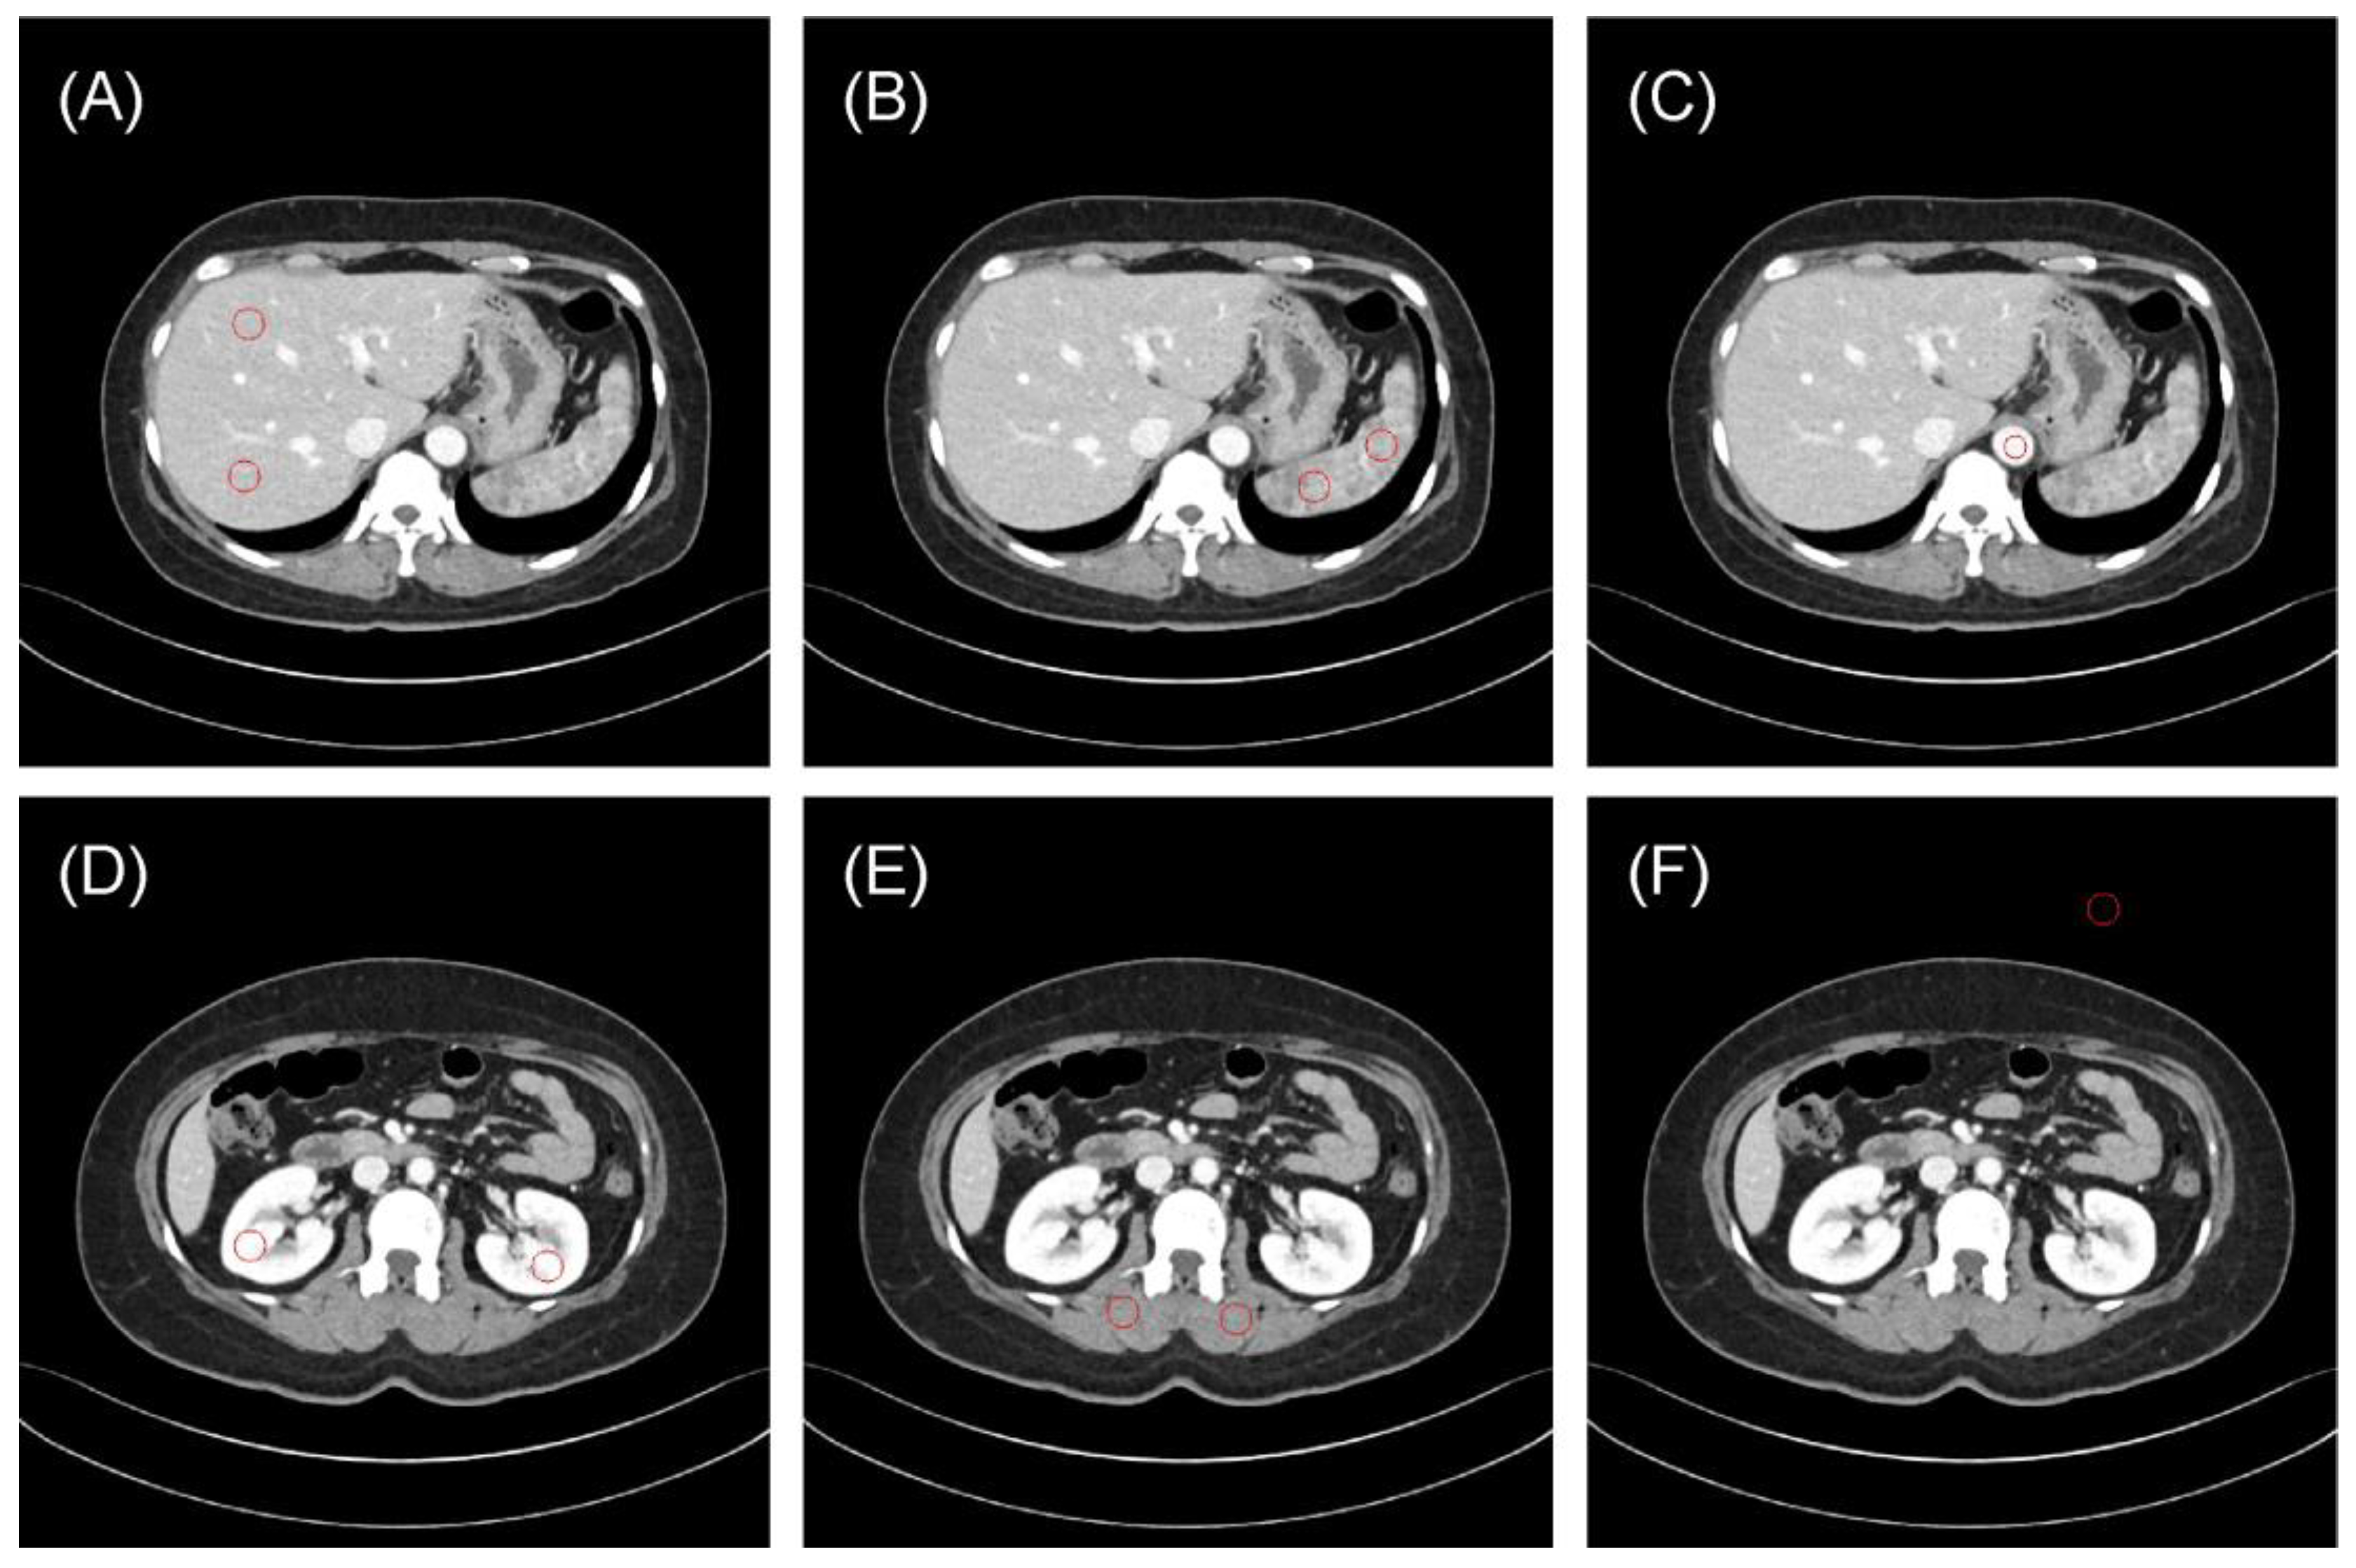

3.1. Region-Based Reproducibility Analysis

3.2. Patient-Based Reproducibility Analysis

3.3. Standard Deviation Map